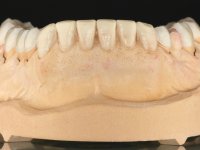

Realizado o diagnóstico e tomada a decisão quanto ao tratamento a executar, tornou-se importante definir qual a sequência de trabalho a adotar no sentido de conseguir a reabilitação da D.V.O. (V.D.O), de forma progressiva e equilibrada. Na primeira fase fez-se uma pré-impressão da arcada inferior com silicone tipo “putty” e em seguida realizou-se o preparo dentário de todo o sector posterior. O preparo para os overlays foi feito coronalmente à linha amelo cementaria no sentido de ser o mais conservador possível. A impressão foi feita com técnica de dupla mistura após afastamento gengival realizado com pasta de caulino. A provisória foi realizada com resina composta de polimerização dual. Em laboratório foram realizados os overlays após se ter aberto ligeiramente (1,5mm) a D.V.O. nos modelos montados em articulador semi-ajustável. Simultaneamente o sector antero-inferior foi encerado no sentido de acompanhar este aumento da D.V.O. Também foi confecionada uma chave de silicone translucido para posterior confeção dos provisórios antero-inferiores. Em boca foi primeiro realizada a provisionalização dos dentes anteriores utilizando resina composta previamente aquecida após preparação das superfícies dentárias para a adesão. Foi colocado o dique de borracha para promover o isolamento absoluto e posteriormente foram colados os overlays. Em laboratório foi realizada nova chave de silicone para confecionar os provisórios antero-superiores. Seguidamente em boca foram preparados os seis dentes antero-superiores após colocação do fio de afastamento gengival. Feita a preparação adequada das superfícies dentárias foi realizada a impressão com técnica de dupla mistura e a respetiva provisória. Em laboratório foram confecionadas 6 facetas feldespáticas num modelo de trabalho tipo “Geller”. A provisória foi removida e as facetas foram coladas em boca utilizando um isolamento relativo competente. Esta opção foi tomada em virtude de uma prévia experiencia negativa com a colocação do dique de borracha na mandibula. Após a colagem dos laminados antero-superiores foram dadas 12 semanas para avaliar a adaptação do paciente à nova situação e então iniciar a confeção das facetas antero-inferiores. Após colocação do fio de afastamento gengival. foram feitos os preparos dentários adequados e em seguida foi feita a impressão. Também foi feita a preparação do dente 3.4 que, entretanto, tinha sofrido uma fratura do overlay. As facetas e a restauração do 3.4 foram realizadas num modelo de trabalho tipo “Geller”. Após remoção da provisória, as facetas foram coladas em boca, utilizando um isolamento relativo pelas razões apontadas anteriormente. Após colocação do trabalho o paciente foi reabilitado por outros colegas com um implante na zona do 2.6 e substituição da coroa aparafusada sobre o implante colocado no local do 3.5. Posteriormente surgiram fraturas nos overlays dos dentes 4.7 e 3.7 que foram reabilitados com overlays em Zr.